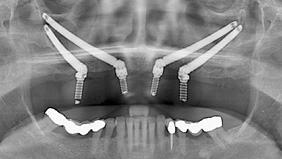

- Surgical Phase

- 2 Zygomatic Implants $5,000 USD + 2 Regular Implants $1,800 USD

- Anesthesionlogist conscious IV sedation

$500 USD - Hospital fees (includes 1 day stay)

$1,500 USD - Temporary Denture

$580 USD - Restorative Phase

- Permanent Denture

- 4 Zygomatic Implant

$10,000 USD - Anesthesionlogist conscious IV sedation

Zygomatic Dental Implants

Zygomatic dental implants are implants that are much longer than conventional implants (40 mm – 50 mm), and are placed in the dense Zygoma bone or otherwise known as the cheekbone.